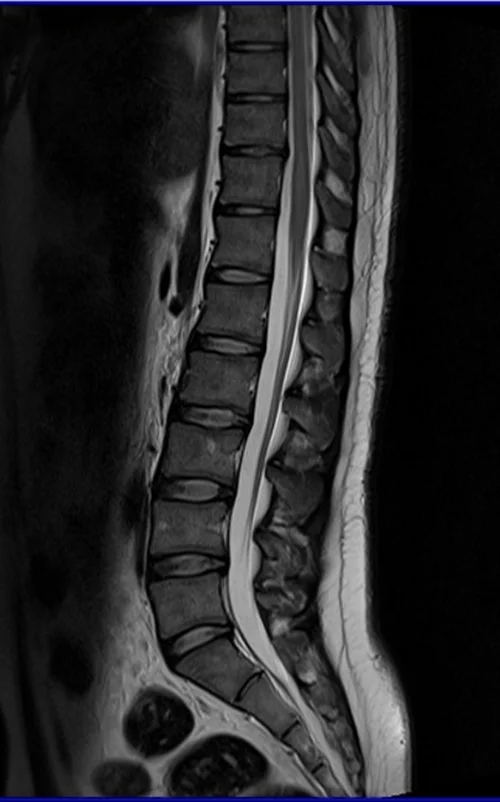

l spine sag t2 image 3 - MRI